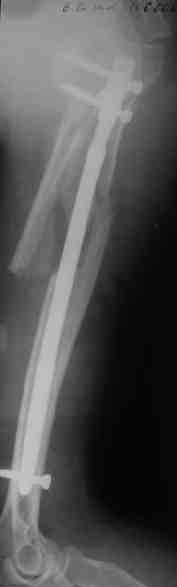

Уважаемые коллеги.

Прооперировали больную с переломом плеча все же гвоздем, Фото в приложении.

Интересно, а канал рассверливали?

Гвоздик похоже ЦИТОвский?

Полагаю, бабушку можно поздравить с обретением

независимости. Судя по снимкам, неврологических расстройств нет и такая пациентка выпишется после снятия швов.

Какие рекомендации Вы дадите этой женщине на ближайшие 6 месяцев?

> Интересно, а канал рассверливали?

минимально

> Гвоздик похоже ЦИТОвский?

точно

НЗ> Интересно, а канал рассверливали?

Только сформировали канал в головке. Диафиз не рассверливали. Хотя при необходимости, конечно, рассверлили бы.

НЗ> Гвоздик похоже ЦИТОвский?

Гвоздь большеберцовый нашей модификации, действительно, их делает предпричятие "ЦИТО". Тут взят 9 мм, укорочен до 240 мм, сделано дополнительное отверстие самое проксимальное, ну и для дистального винта.

НЗ> независимости. Судя по снимкам, неврологических расстройств

НЗ> нет и такая пациентка выпишется после снятия швов.

Неврологии нет, а выписать можно хоть на второй день, швы можно снять и в местной больнице.

НЗ> Какие рекомендации Вы дадите этой женщине на ближайшие 6 месяцев?

Почему так надолго? На ближэайшие недели - разработка движений, и все. Полагаю, что недель после 4 никаких рекомендаций не будет нужно, просто жить обычной жизнью сельской пенсионерки.